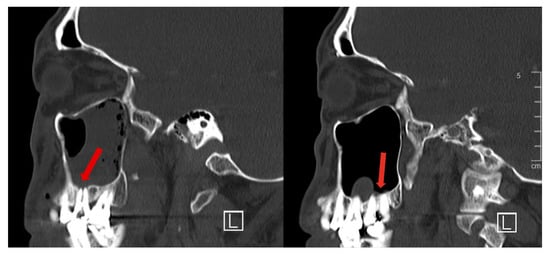

During follow-up, the necrotic sinus mucosa was eventually replaced by granulation tissue (Figure 5). One month post-injury, the symptoms which bothered the patient most were the residual burning sensation during sinus irrigation and persistent left cheek numbness. Sinus mucosa recovered clinically after three months but cheek numbness persisted. There were no ophthalmic sequelae.

Figure 5.

(a) Endoscopic clinical image of the left maxillary sinus at one week post-operation, viewed with a 45-degree-angled scope. Remnant dusky mucosa is seen with some slough and granulation; (b) Endoscopic clinical image of the left maxillary sinus at one month post-operation, viewed with a 45-degree-angled scope. Mucosa and slough were mostly replaced by granulation.